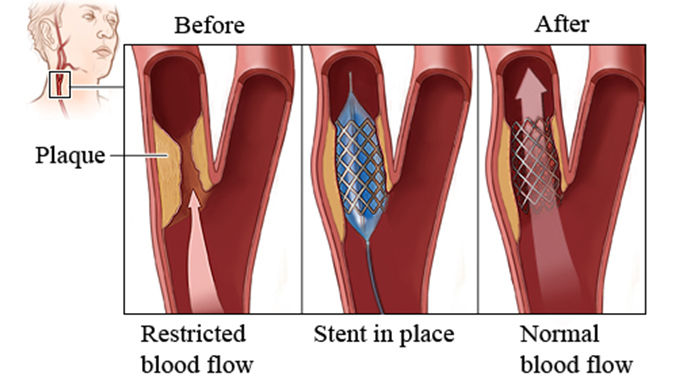

Υπάρχουν δύο μορφές θεραπείας:- Μπαλονάκι με στεντ

Σύμφωνα με διεθνείς μελέτες και τις σύγχρονες κατευθυντήριες οδηγίες φαίνεται ότι στις περισσότερες των περιπτώσεων λιγότερο επικίνδυνο είναι το χειρουργείο ενδαρτηρεκτομής. Βέβαια στη φαρέτρα του αγγειοχειρουργου, υπάρχει και η αποκατάσταση με στεντ αφού κάθε ασθενής έχει την ιδιαιτερότητα του.Ο διεγχειρητικός κίνδυνος εγκεφαλικού ή θανάτου είναι 1.5% για την ενδαρτηρεκτομή και 2% για το στεντ σε ασυμπτωματική νόσο. Η αντιμετώπιση της νόσου μπορεί να είναι συντηρητική στα αρχικά στάδια, με ρύθμιση των παραγόντων κινδύνου και παρακολούθηση, ενώ στα τελικά στάδια η αντιμετώπιση πρέπει να είναι χειρουργική. Υπάρχει σε επιλεγμένες περιπτώσεις και η ενδαγγειακή προσέγγιση, με τοποθέτηση ενδονάρθηκα μέσα στην καρωτίδα.

Στένωση δεξιάς Καρωτίδας ΣΥΜΦΩΝΑ ΜΕ ΔΙΕΘΝΕΙΣ ΜΕΛΕΤΕΣ ΚΑΙ ΤΙΣ ΣΥΓΧΡΟΝΕΣ ΚΑΤΕΥΘΥΝΤΗΡΙΕΣ ΟΔΗΓΙΕΣ ΦΑΙΝΕΤΑΙ ΟΤΙ ΣΤΙΣ ΠΕΡΙΣΣΟΤΕΡΕΣ ΤΩΝ ΠΕΡΙΠΤΩΣΕΩΝ ΛΙΓΟΤΕΡΟ ΕΠΙΚΙΝΔΥΝΟ ΕΙΝΑΙ ΤΟ ΧΕΙΡΟΥΡΓΕΙΟ ΕΝΔΑΡΤΗΡΕΚΤΟΜΗΣ. ΣΕ ΚΑΘΕ ΠΕΡΙΠΤΩΣΗ ΣΤΗ ΦΑΡΕΤΡΑ ΤΟΥ ΑΓΓΕΙΟΧΕΙΡΟΥΡΓΟΥ, ΥΠΑΡΧΕΙ ΚΑΙ Η ΑΠΟΚΑΤΑΣΤΑΣΗ ΜΕ ΣΤΕΝΤ ΑΦΟΥ ΚΑΘΕ ΑΣΘΕΝΗΣ ΕΧΕΙ ΤΗΝ ΙΔΙΑΙΤΕΡΟΤΗΤΑ ΤΟΥ.

ΠΩΣ ΓΙΝΕΤΑΙ ΤΟ ΣΤΕΝΤ;

Υπό τοπική αναισθησία γίνεται παρακέντηση της αρτηρίας του μηρού και προώθηση συρμάτων και καθετήρων μέχρι τη βλάβη. Η διαδικασία γίνεται σε αγγειοχειρουργική σουίτα με αγγειογράφο και υπό ακτινοσκόπηση. Ο ασθενής επιστρέφει στο κρεβάτι και παίρνει εξιτήριο σε μία ημέρα.